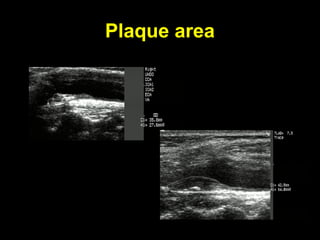

Plaque area

Plaque volume